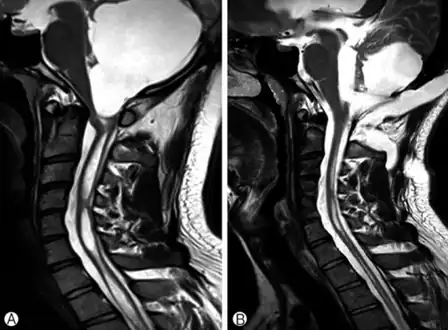

a)Large cystic mass at the posterior fossa with compression of the 4th ventricle b) postoperative MRI, a residual cyst and syringomyelia was decreased. -

Surgery of the spinal cord has certain characteristic risks associated with it, and the benefits of a surgical procedure on the spine have to be weighed against the possible complications associated with any procedure. Surgical treatment is aimed at correcting the condition that allowed the syrinx to form. It is vital to bear in mind that the drainage of a syrinx does not necessarily mean the elimination of the syrinx-related symptoms but rather is aimed at stopping progression. In cases involving an Arnold–Chiari malformation, the main goal of surgery is to provide more space for the cerebellum at the base of the skull and upper cervical spine without entering the brain or spinal cord. This often results in flattening or disappearance of the primary syrinx or cavity, over time, as the normal flow of cerebrospinal fluid is restored. If a tumor is causing syringomyelia, removal of the tumor is the treatment of choice, if this is considered to be safe.